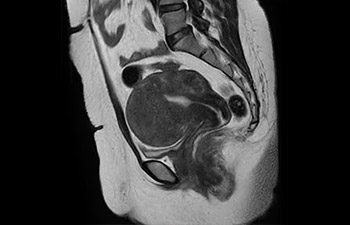

com Compressed SENSE

A equipe de IRM do Hospital Central Kurashiki incorporou o Compressed SENSE à maioria dos protocolos de exames do cérebro, coluna, abdômen e coração do seu Ingenia 1.5T, o que resultou em varreduras de IRM mais rápidas e de alta qualidade, um resultado apreciado por pacientes e pela equipe.